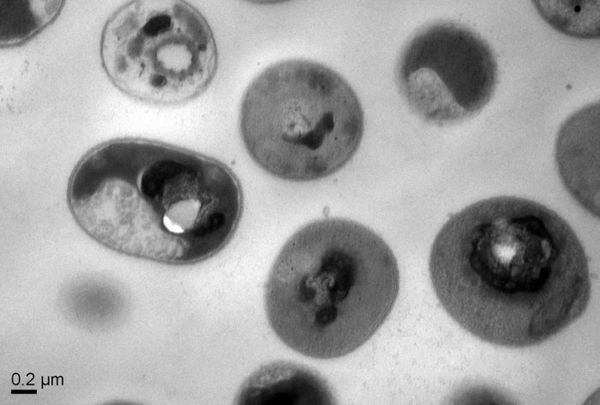

鎹濯掓姤閬擄紝鐢辨柊鍔犲潯縐戝鎶鏈爺絀跺眬(A*STAR)涓嬪睘鐢熺墿宸ョ▼鍜岀撼綾蟲妧鏈爺絀舵墍錛圛BN錛夌殑縐戝瀹朵互鍙奍BM鐮旂┒鎵縐戝瀹剁粍鎴愮殑鐮旂┒灝忕粍宸茬粡寮鍙戝嚭浜嗕竴縐嶆柊鐨勫悎鎴愬垎瀛愶紝鍙互闈跺悜鍜屾潃姝諱簲縐嶈愬鑽粏鑿屻傝繖縐嶅悎鎴愯仛鍚堢墿琚彂鐜版槸鏃犳瘨鐨勶紝騫朵笖鍙互浣垮叏鏂扮殑娌葷枟鍓傜被鍨嬭兘澶熻В鍐蟲棩鐩婁弗閲嶇殑鑰愭姉鐢熺礌瓚呯駭緇嗚弻闂銆?/span>

鍚堟垚鍒嗗瓙琚О涓鴻儘瀹樿兘鍖栬仛紕抽吀閰紝琚彂鐜版棦鍙敓鐗╅檷瑙e張瀵逛漢浣撶粏鑳?yōu)鏃犳瘨銆傚疄璐ㄤ笂錛屽甫姝g數鐨勫悎鎴愯仛鍚堢墿榪涘叆媧諱綋騫墮氳繃瀵煎叆寰敓鐗╄啘鐨勭浉鍏寵礋鐢佃嵎鑰岀壒寮傛х粨鍚堟煇浜涚粏鑿岀粏鑳?yōu)銆備竴鏃︿笌緇嗚弻榪炴帴錛岃仛鍚堢墿絀胯繃緇嗚優(yōu)鑶滃茍瑙﹀彂緇嗚優(yōu)涓泲鐧借川鍜孌NA鐨勫浐鍖栵紝鏉姝葷粏鑿屻?/span>

璇ョ爺絀剁殑浣滆呬箣涓Yi Yan Yang琛ㄧず錛氣滄垜浠凡緇忚瘉鏄庝簡鐢熺墿鍙檷瑙e悎鎴愬ぇ鍒嗗瓙鐨勭涓涓緥瀛愶紝璇ュ悎鎴愬ぇ鍒嗗瓙鍦ㄥ皬榧犱腑鍏鋒湁騫胯氨鎶楄弻媧繪э紝鐙壒鐨勬潃浼ゆ満鍒跺拰鏃犳瘨鎬с備竴鏃﹁仛鍚堢墿鏉姝葷粏鑿屽畬鎴愬叾宸ヤ綔錛屽畠?yōu)畣鍦ㄤ笁澶╁悗鑷剦櫃嶈В迤堜笖涓嶄細鐣欏湪浣撳唴锛寴q欑鎶楀井鐢熺墿鍓傚娌葷枟鍜岄闃插閲嶈愯嵂鎬у叏韜劅鏌撴樉紺哄嚭寰堝ぇ鐨勫笇鏈涖傗?

鍦ㄥ皬榧犲疄楠屼腑錛岃繖浜涘垎瀛愭垚鍔熷湴娑堢伃浜嗕笘鐣屽悇鍦板尰闄腑鍙戠幇鐨勪簲縐嶅父瑙佽秴綰х粏鑿屻傝榪囩▼鍦ㄥ皬榧犱腑娌℃湁鏄劇ず鍑烘瘨鎬х殑鏄捐憲榪硅薄錛屽茍涓斿湪澶氭澶勭悊鍚庯紝緇嗚弻娌℃湁鏄劇ず瀵硅仛鍚堢墿浜х敓鎶楁х殑榪硅薄銆?